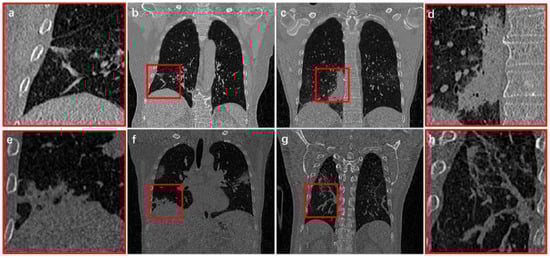

Since CT images can collect 3D information of patients, it is currently the most commonly clinical imaging technique for COVID-19 examination [15,16,17,18]. From CT images, COVID-19 infection present characteristics of regional spread, blurred boundaries, tissue adhesion, and large morphological differences (Figure 1). Therefore, identifying the method of how to extract infection effectively and accurately from COVID-19 CT images is a difficult and urgent challenge [19,20].

Although initial results have been achieved in reconstruction of COVID-19 infection, there are still some problems that still need to be solved: (1) When infections are adjacent to thorax, segmentation boundary cannot be effectively judged (Figure 1c); (2) Most methods focus on 2D images processing or partial patches, which cannot deal with complete 3D feature information in CT images; (3) COVID-19 infection usually only occupies a small part of the entire CT image. Thus, imbalance of positive and negative samples appears in network training, resulting in slow convergence and insufficient accuracy; (4) In vicinity of infected area, invasive structure of infection adheres to vessels and tracheas, which is difficult to distinguish effectively (Figure 1d).

Figure 1. Infection structure from COVID-19 CT images. (b,c,f,g) indicate four different cases. (a,d,e,h) are the local magnification structure of the red boxes from (b,c,f,g), respectively.